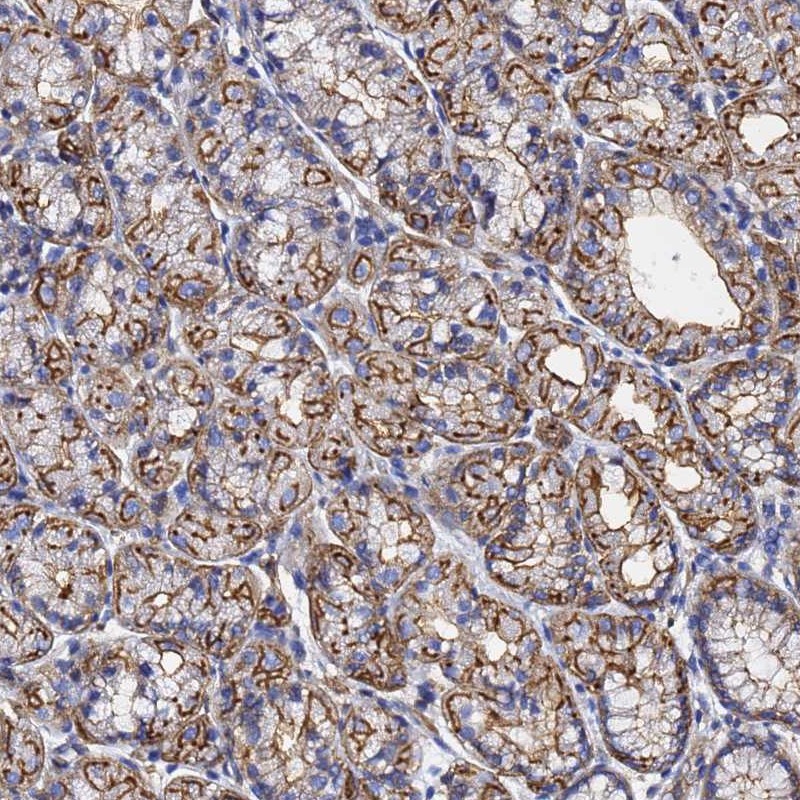

Immunohistochemical staining of human stomach, upper shows strong membranous positivity in glandular cells.